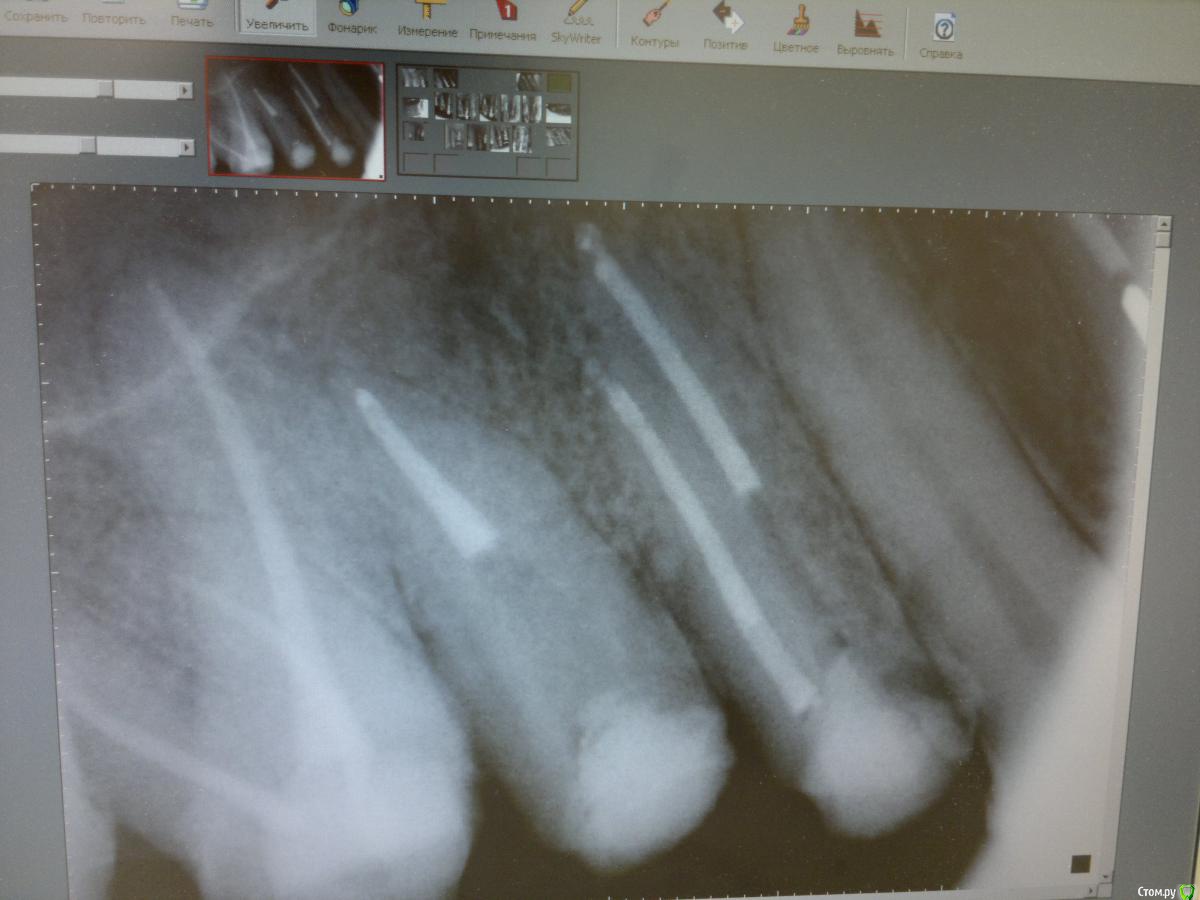

Ico Опубликовано 2 июня, 2016 Поделиться Опубликовано 2 июня, 2016 Штифты чаще меньше, чем заявленный размер, поэтому не калибрую добавочные Даже №30 не помню уже когда и брал. Все чаще 25ым обхожусь. .Примерно так же.Но бывают и исключения,и они хорошо видны на снимке,как будто не отжал на определенном участке канала,а это как раз мог быть тот заветный добавочный штифт который ел после 18)))) 1 Ссылка на комментарий